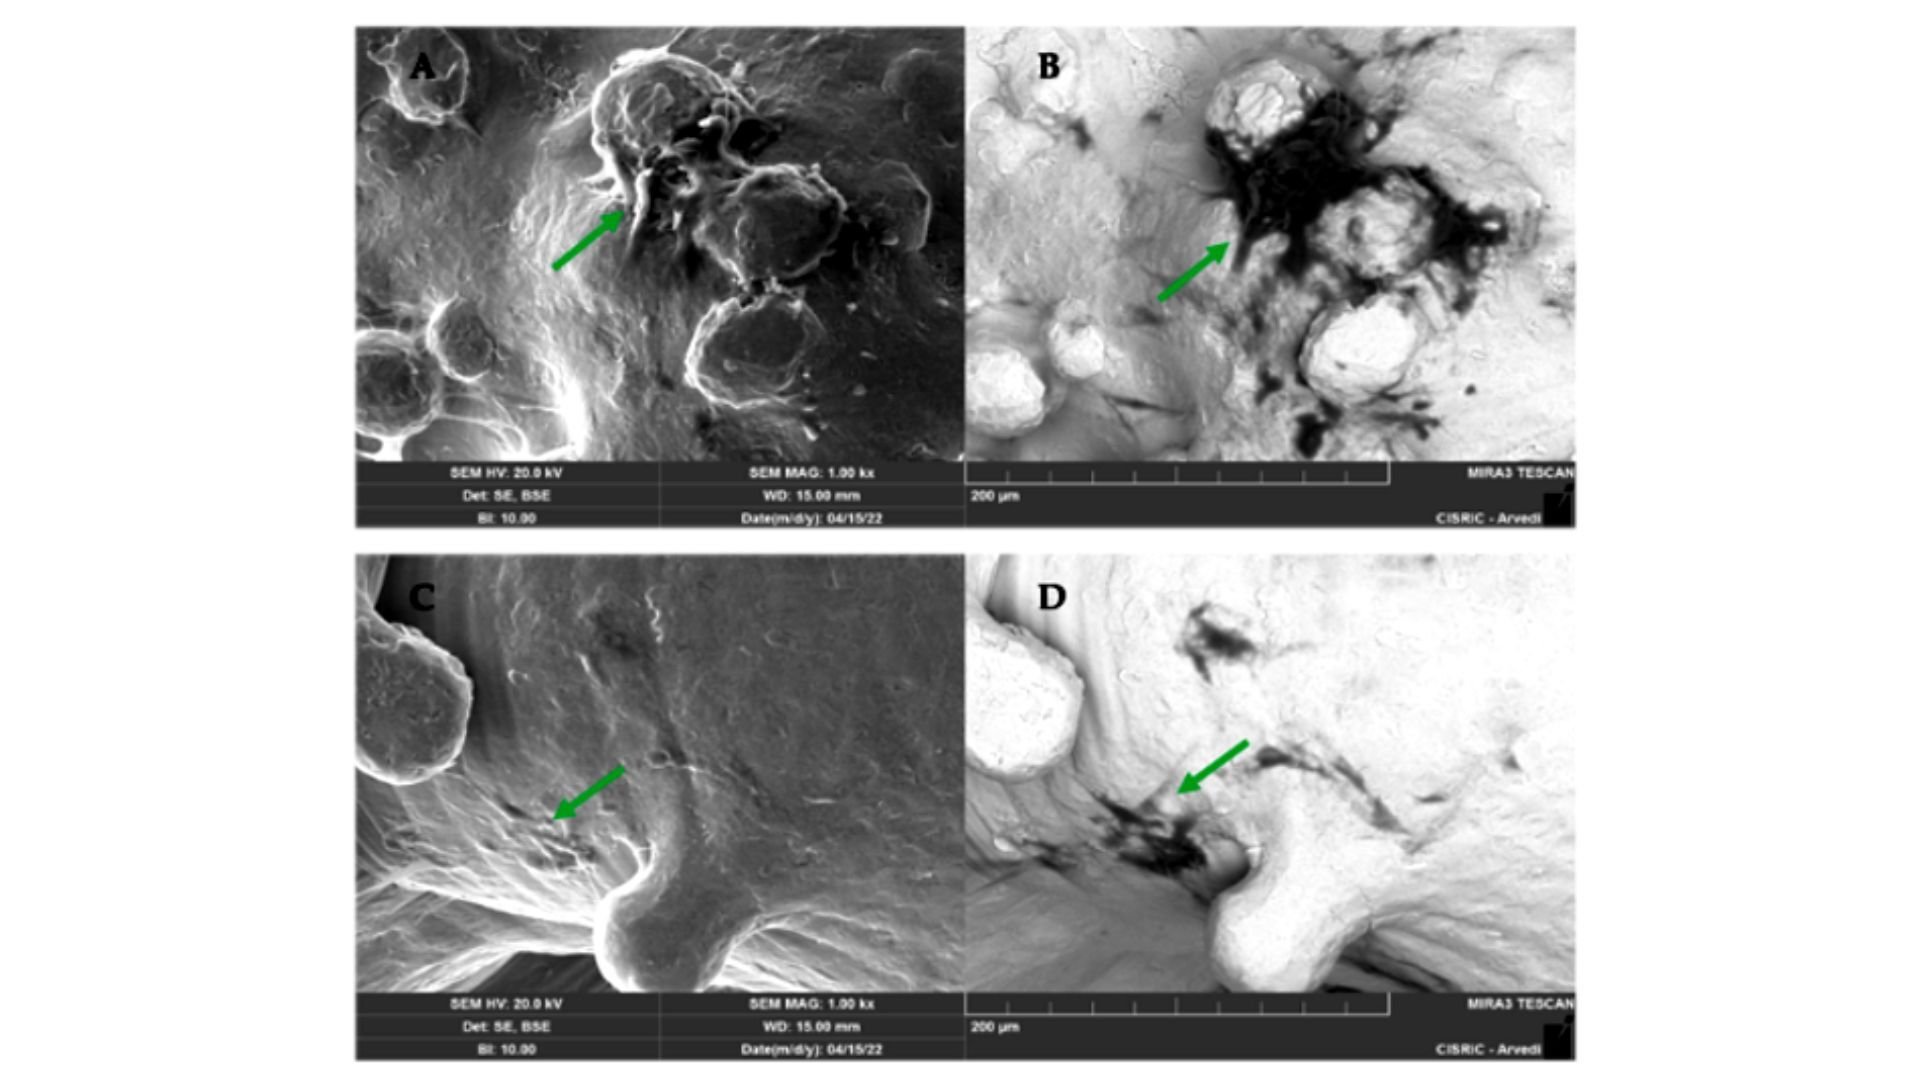

Key findings from the study confirm that Trabecular Titanium 3D scaffold supports human adipose-derived mesenchymal stem cell colonization and induces their differentiation into bone forming cells (osteoblasts) with the deposition of the abundant mineralized extracellular matrix.

in vitro_TTThe osteoinductive behavior was observed regardless of the additive manufacturing process technology used, demonstrating that the preservation of TT specific micro- and macro-design features is the key factor driving the enhanced biological response.